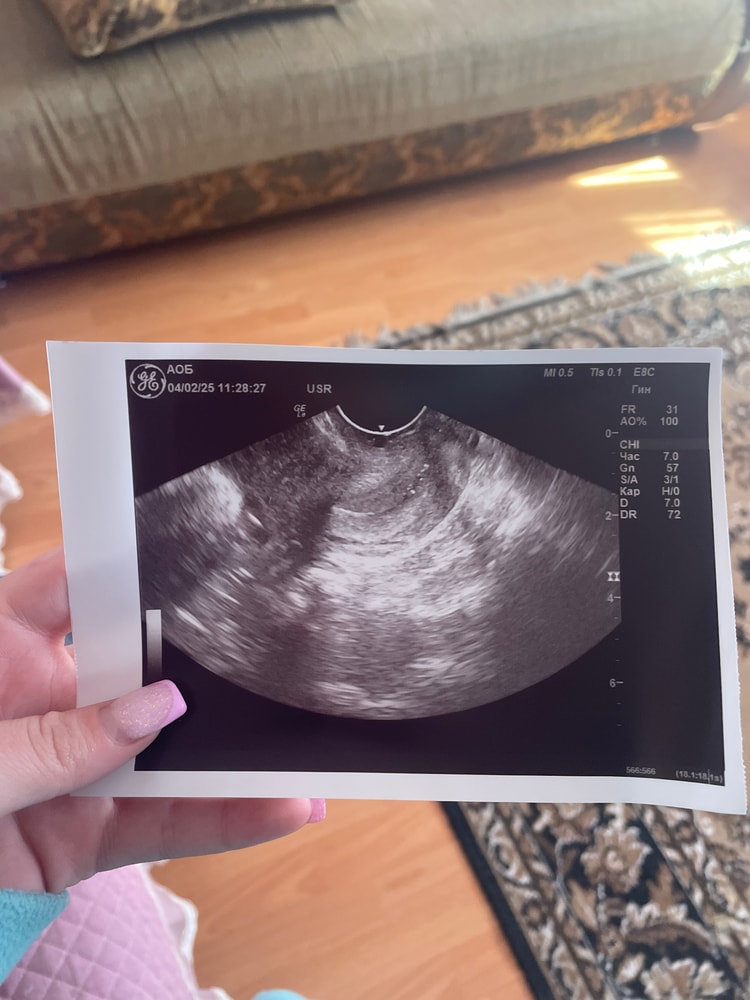

на узи обычном ничего не увидели, я подумала либо еще рано, либо я себе внушаю просто) ну как это бывает.. отправили на ТВИ там есть окошечко сказали в нем полоса, пыталась узнать что это, как и писала выше конкретного ответа не получила, я конечно решила еще ждать, но в то же время с кем то посоветоваться

есть снимок узи, и в общем заключение, файл прикрепить сюда не могу к сожалению